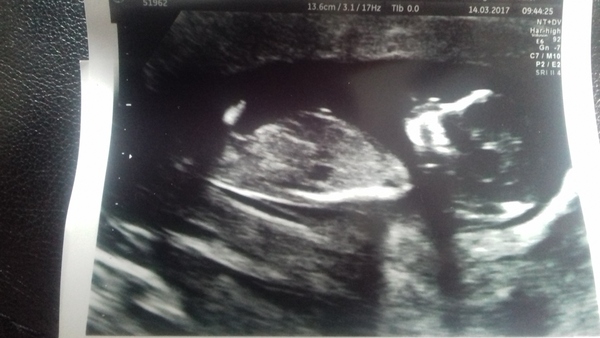

Had scan this morning. All looking good. Baby wouldn't stop moving and kept rolling over / turning upside down while they were trying to take measurements - just like DD.

They measured me at 12+6 instead today so that moves my due date up 3 days to 20th September.

Had my scan. All was fine which is great. Such a relief! Date moved forward by 4 days. I look massive but I showed really early with my first too.